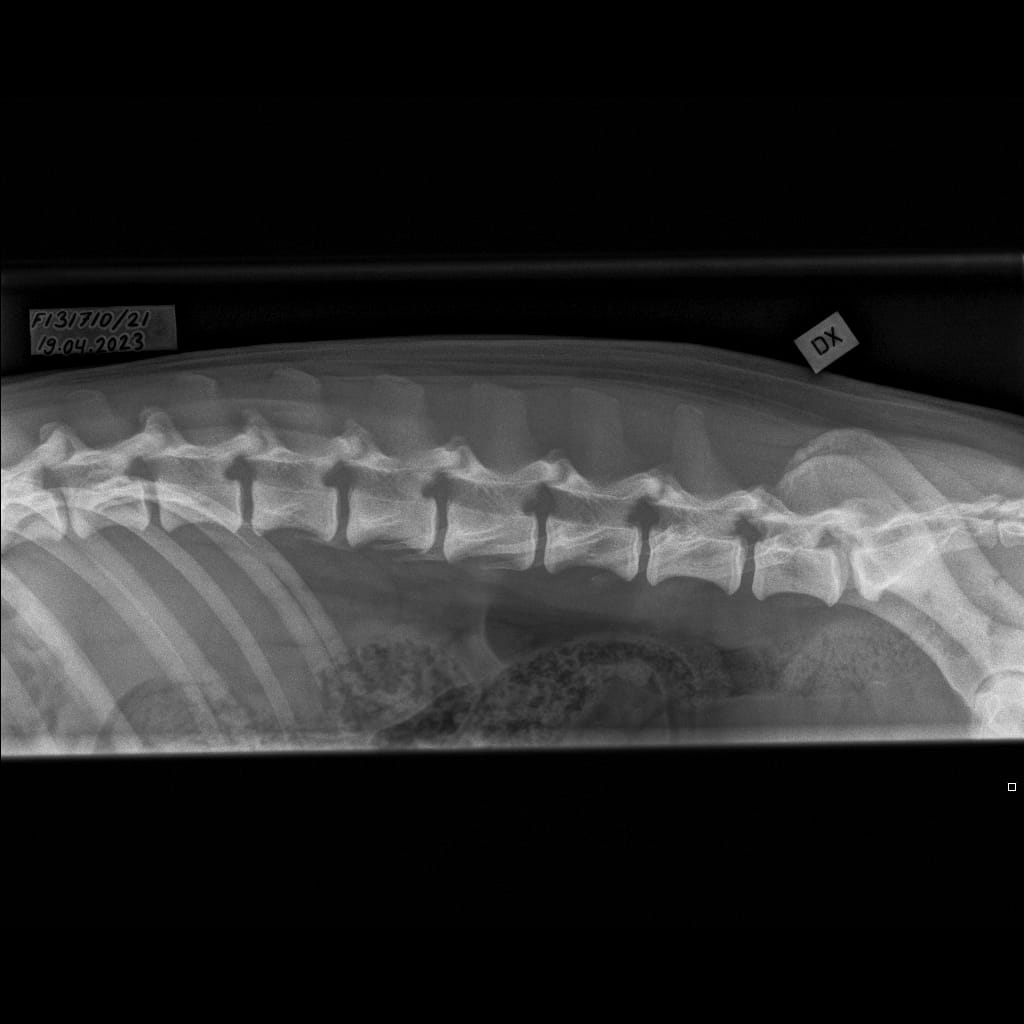

Lumbosacral transitional vertebra (LTV) in Rhodesian Ridgebacks

Selkäranka -Lanneranka LAT-6.11.2023-16_02_21-719